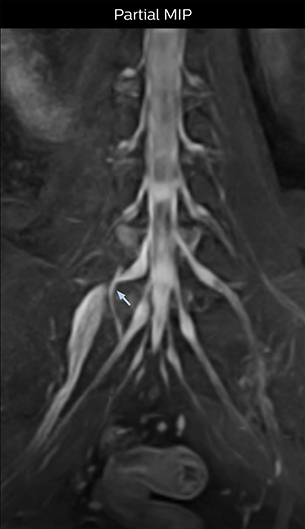

“In such case, we would then browse through axial T2-weighted MR images slice by slice and mentally reconstruct the actual situation based on both radiculography and MRI. Fortunately, NerveVIEW can now very well show nerve courses and presence of nerve compression or edema in one single image series.” “We have often seen NerveVIEW directly depict details of the nerve compression that were not observed by radiculography. Therefore, we think that with NerveVIEW we can reduce the number of invasive examinations, especially for some patients with lumbar plexus symptoms.”

“Before NerveVIEW, diagnosis by MRI alone was sometimes difficult, unless there was a strong suspicion based on clinical symptoms,” says Shoji Yabuki, MD, DMSc, Orthopedic surgeon at Fukushima Medical University School of Medicine. “This is why we routinely perform selective lumbosacral radiculography (nerve root block) and x-ray in such cases. However, radiculography can only depict nerves as far as the contrast agent reaches. When a nerve is distorted by compression, the contrast agent will not pass through this compressed area, preventing us from evaluating the full nerve compression.”

The key concept in MR neurography, Dr. Yabuki stresses, is the ability to directly visualize spinal nerves, versus inferring the presence of pathology indirectly. “Before NerveVIEW, we estimated compression of the nerve by looking for the presence or absence of fat signal on other MR images,” he says.

“For example, in sagittal images, when the presence of fat is observed in the intervertebral foramen, it suggests that there is a margin around the nerve. Similarly, the absence of fat indicates that the nerve is being compressed. So, we used to deduce nerve compression indirectly. With NerveVIEW, however, we can observe the condition of the nerves directly, regardless of the presence or absence of fat. We always prefer such direct observation of anatomy over having to make an inference about it.”